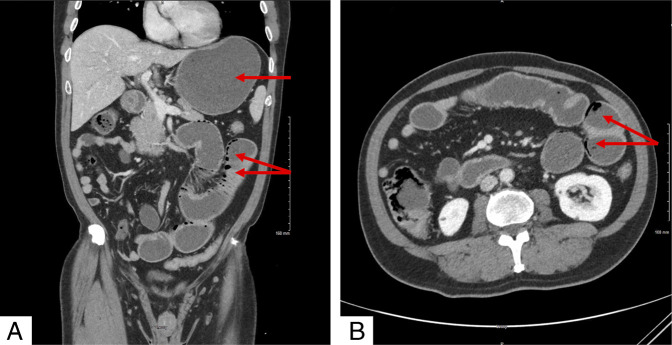

如果处理不当,结肠镜检查前的肠道准备会导致严重的并发症。我们报告一个53岁的男性病例,由于用药错误,将聚乙二醇与车前草混淆,导致小肠梗阻和肠肺病。虽然车前草通常是安全的,但如果大量摄入会引起梗阻。虽然患者对保守治疗反应良好,但本病例显示了泻药滥用的严重并发症。明确的患者教育对于结肠镜检查前肠道准备的安全性和有效性至关重要。

Bowel preparation for colonoscopy can lead to severe complications if mismanaged. We present a case of a 53-year-old man who developed small bowel obstruction and pneumatosis intestinalis due to a medication error, confusing polyethylene glycol with psyllium. While generally safe, psyllium is known to cause obstruction if ingested in large quantities. While the patient responded well to conservative treatment, this case demonstrates a serious complication of laxative misuse. Clear patient education is essential for the safety and efficacy of bowel preparation before colonoscopy.